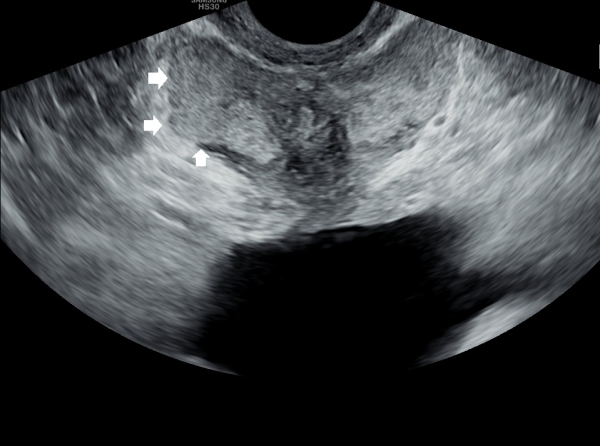

내원 당일 경직장 전립선 초음파 검사상 오랜 세월동안 사정관의 벽이 수명을 다한 거짓 중층 원주 상피 세포가 탈락되어 사정관 입구에 막혀 두텁게 쌓여 있고 요도에도 탈락된 상피 세포가 쌓여서 정낭과 정관 그리고 전립선액 과 배뇨등의 순환 장애를 보이고 있는 경직장 전립선 초음파 사진입니다.

This transrectal prostate ultrasound image, taken on your first visit, shows that over many years, the wall of the ejaculatory duct has been blocked by a buildup of old, shed pseudostratified columnar epithelial cells. These cells have accumulated at the opening of the ejaculatory duct and in the urethra, leading to circulation problems in the seminal vesicles, vas deferens, and prostate fluid, as well as urinary flow issues.